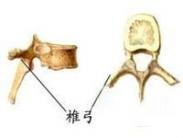

椎弓结核

628健康网为您分享有关椎弓结核的症状,椎弓结核的治疗方法,椎弓结核的预防知识,椎弓结核的症状图片,椎弓结核吃什么药,椎...